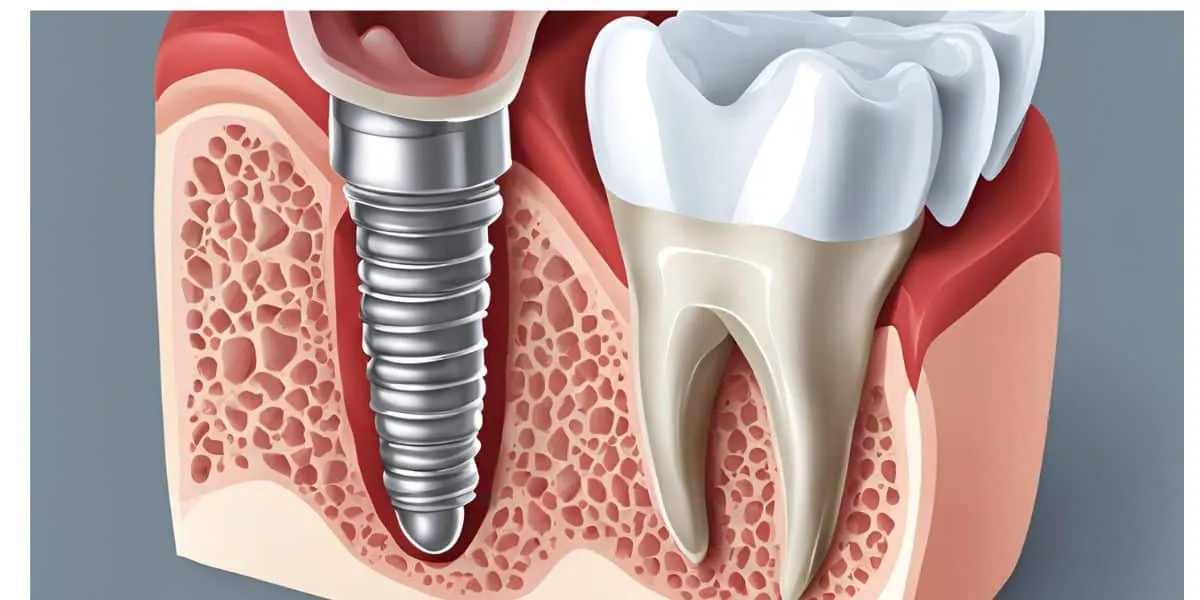

Un implante dental es una pequeña pieza de en la mayoría de los casos fabricada de un material biocompatible o bio-inerte llamado Titanio.

El implante va en el lugar donde antes había una raíz de un diente que se ha perdido y hace las veces de ésta.

Son muy parecidos a un perno o tornillo, pero en su cabeza tiene la posibilidad de atornillar acoples (aditamentos) para conectar prótesis o coronas dentales

Al final queda una especie de diente con tornillo fijo en el lugar que antes ocupaba un diente perdido.

Por su similitud a una raíz dental en términos de forma y en su fijación al hueso, un implante dental es el mejor sustituto que existe para una raíz.

Una vez que el implante se integra al hueso y ocurre el sellado gingival, el implante está listo para albergar acoples o aditamentos que a su vez sirven de soporte a coronas implanto-soportadas o prótesis dentales.